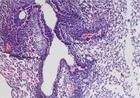

巨胞病毒是由巨細胞病毒引起的一種全身感染性疾病,屬性傳播疾病.為DNA病毒,感染的特徵性病變為感染細胞增大,細胞核和細胞質內分別出現嗜酸性和嗜鹼性包涵體.巨細胞病毒具有潛伏活動的生物學特徵,多為潛伏感染,可因妊娠而被激活。